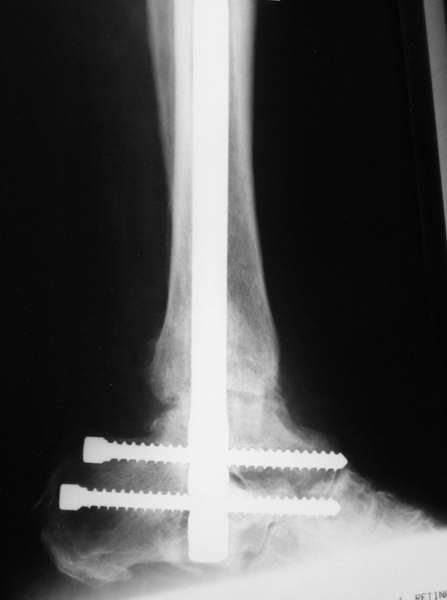

Можно: 65-летняя пациентка, оперирована по поводу несросшегося в гипсе перелома лодыжек с патологической вальгусной установкой стопы и выраженным нарушением опрной функции. Оперирована через 6 месяцев после травмы. Рентгенограммы через 4 месяца после операции.

Уважаемый А.Семенистый. Складывается впечатление, что вы выполнили трехсуставный артродез, уж больно длинные блокирующие винты. Не мешают ли они пациентке при ходьбе?

Да конечно винты длинноваты! Мешают ли ходить? Во всяком случае субьективно пациентка удовлетворена. Ходит, естевственно, хуже чеи до травмы, но намного лучше, чем до операции.